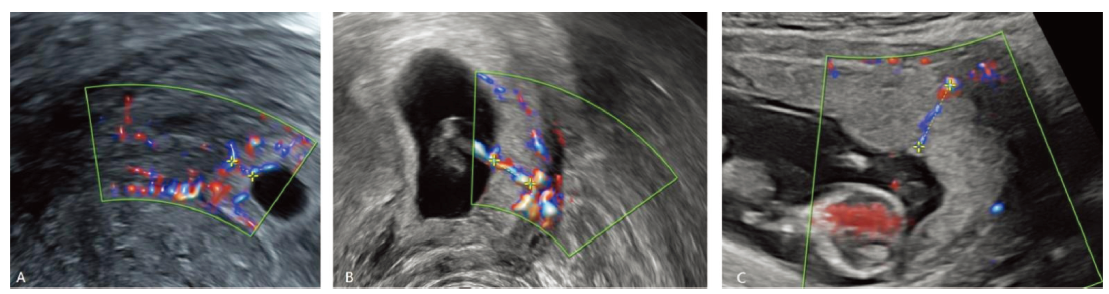

目的: 使用超声HD-Flow模式观察并验证妊娠早期绒毛区优势血流的存在及变化,并探索其与早期自然流产的关系。方法: 对接受体外受精-胚胎移植后成功获得单胎妊娠的女性分别于孕5周、孕7周和孕12~13周行超声检查,测量绒毛区优势血流信号及孕囊、卵黄囊、胎芽和胎心等指标,分析绒毛区优势血流信号随孕龄变化情况;分析该信号长度与早期自然流产的关系。结果: 在接受体外受精-胚胎移植获得妊娠的女性中证实了绒毛区优势血流的存在,该血流信号长度随孕龄增加而增长,优势血流静脉流速和下方蜕膜区螺旋动脉流速随孕龄增加而增长,螺旋动脉阻力指数随孕龄增加而下降;孕5周和孕7周持续妊娠组优势血流信号检出率及长度均显著高于早期自然流产组(P<0.05)。孕7周时,优势血流信号长度<第5百分位数者发生早期自然流产的风险是≥第5百分位数者的10.84倍(OR=10.84,95%CI:6.12~19.22,P<0.001)。结论: 妊娠早期胎盘绒毛区存在优势血流信号,其长度过短可能提示早期自然流产风险增加。